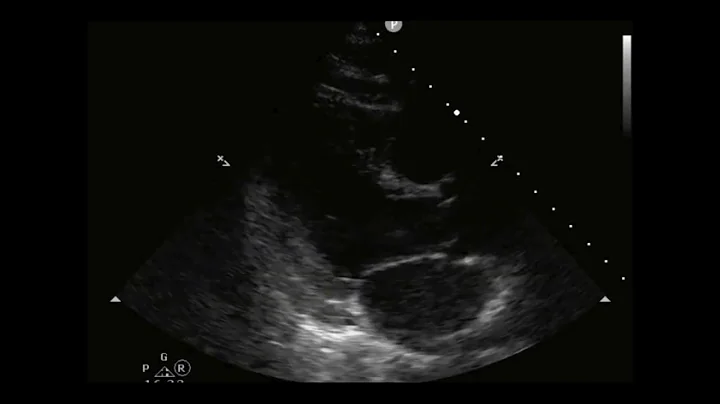

Estimating Ejection Fraction Using Fractional Shortening With Cardiac Ultrasound/echocardiography

Learn how to estimate Left Ventricular Ejection Fraction of the Heart using Fraction Shortening with Cardiac Ultrasound, POCUS, ...